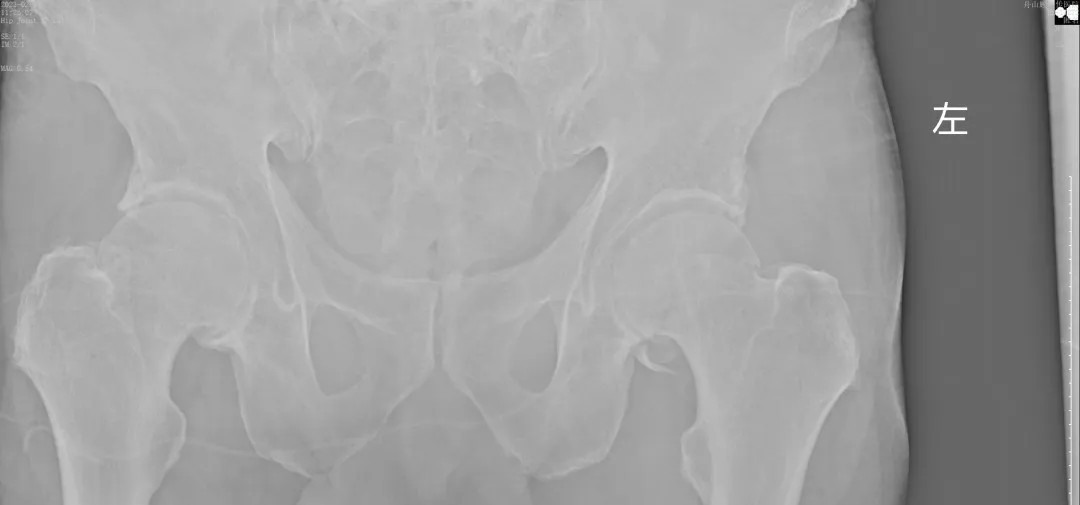

經(jīng)過王副主任認(rèn)真仔細(xì)的檢查,并結(jié)合X線攝片后,他告訴患者及其家屬:“周大爺是外傷導(dǎo)致的急性髖關(guān)節(jié)脫位、髖臼骨折!”一聽脫位骨折了,患者及家屬焦慮萬分,擔(dān)心手術(shù)給身體和經(jīng)濟(jì)帶來的巨大壓力。王副主任耐心告知周大爺一家人:“周大爺這種病情可以保守治療,用我們顧氏的正骨手法可以復(fù)位的,不需要開刀,價(jià)格也實(shí)惠”。家屬聽到不用做手術(shù),瞬間放心不少,表示非常愿意配合治療。

(術(shù)后復(fù)片  關(guān)節(jié)對(duì)位良好)